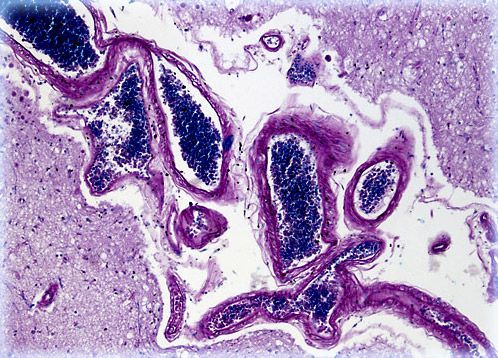

Human Cerebral Cortex

The human cerebrum is divided into two mirror image cerebral hemispheres by the longitudinal fissure. Each of these hemispheres exhibits an outer, wrinkly layer of gray matter known as the cerebral cortex.